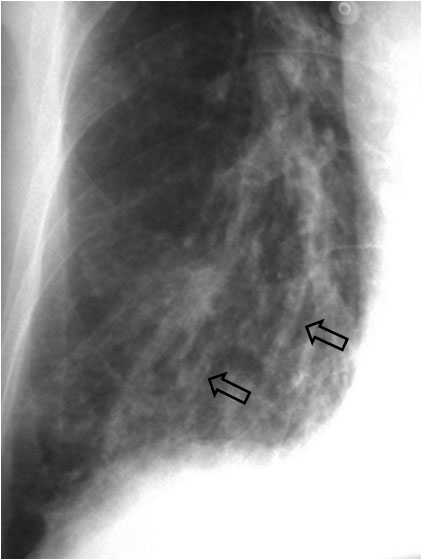

SIGNO DE LAS VÍAS DEL TRANVÍAVIAS2Se trata de otro signo de bronquiectasias. La presencia de imágenes paralelas o ligeramente convergentes, situadas con más frecuencia en los lóbulos inferiores, dirigidas hacia el hilio, corresponde a bronquiectasias tubulares. Las vías corresponden a las paredes engrosadas de los bronquios dilatados (flechas).

Hay que recordar que también existe un Signo de las vías del tranvía en el TEP (el contraste alrededor del trombo), así como en el meningioma del nervio óptico (el realce de la vaina) y en el Síndrome de Sturge-Weber (las calcificaciones corticales).